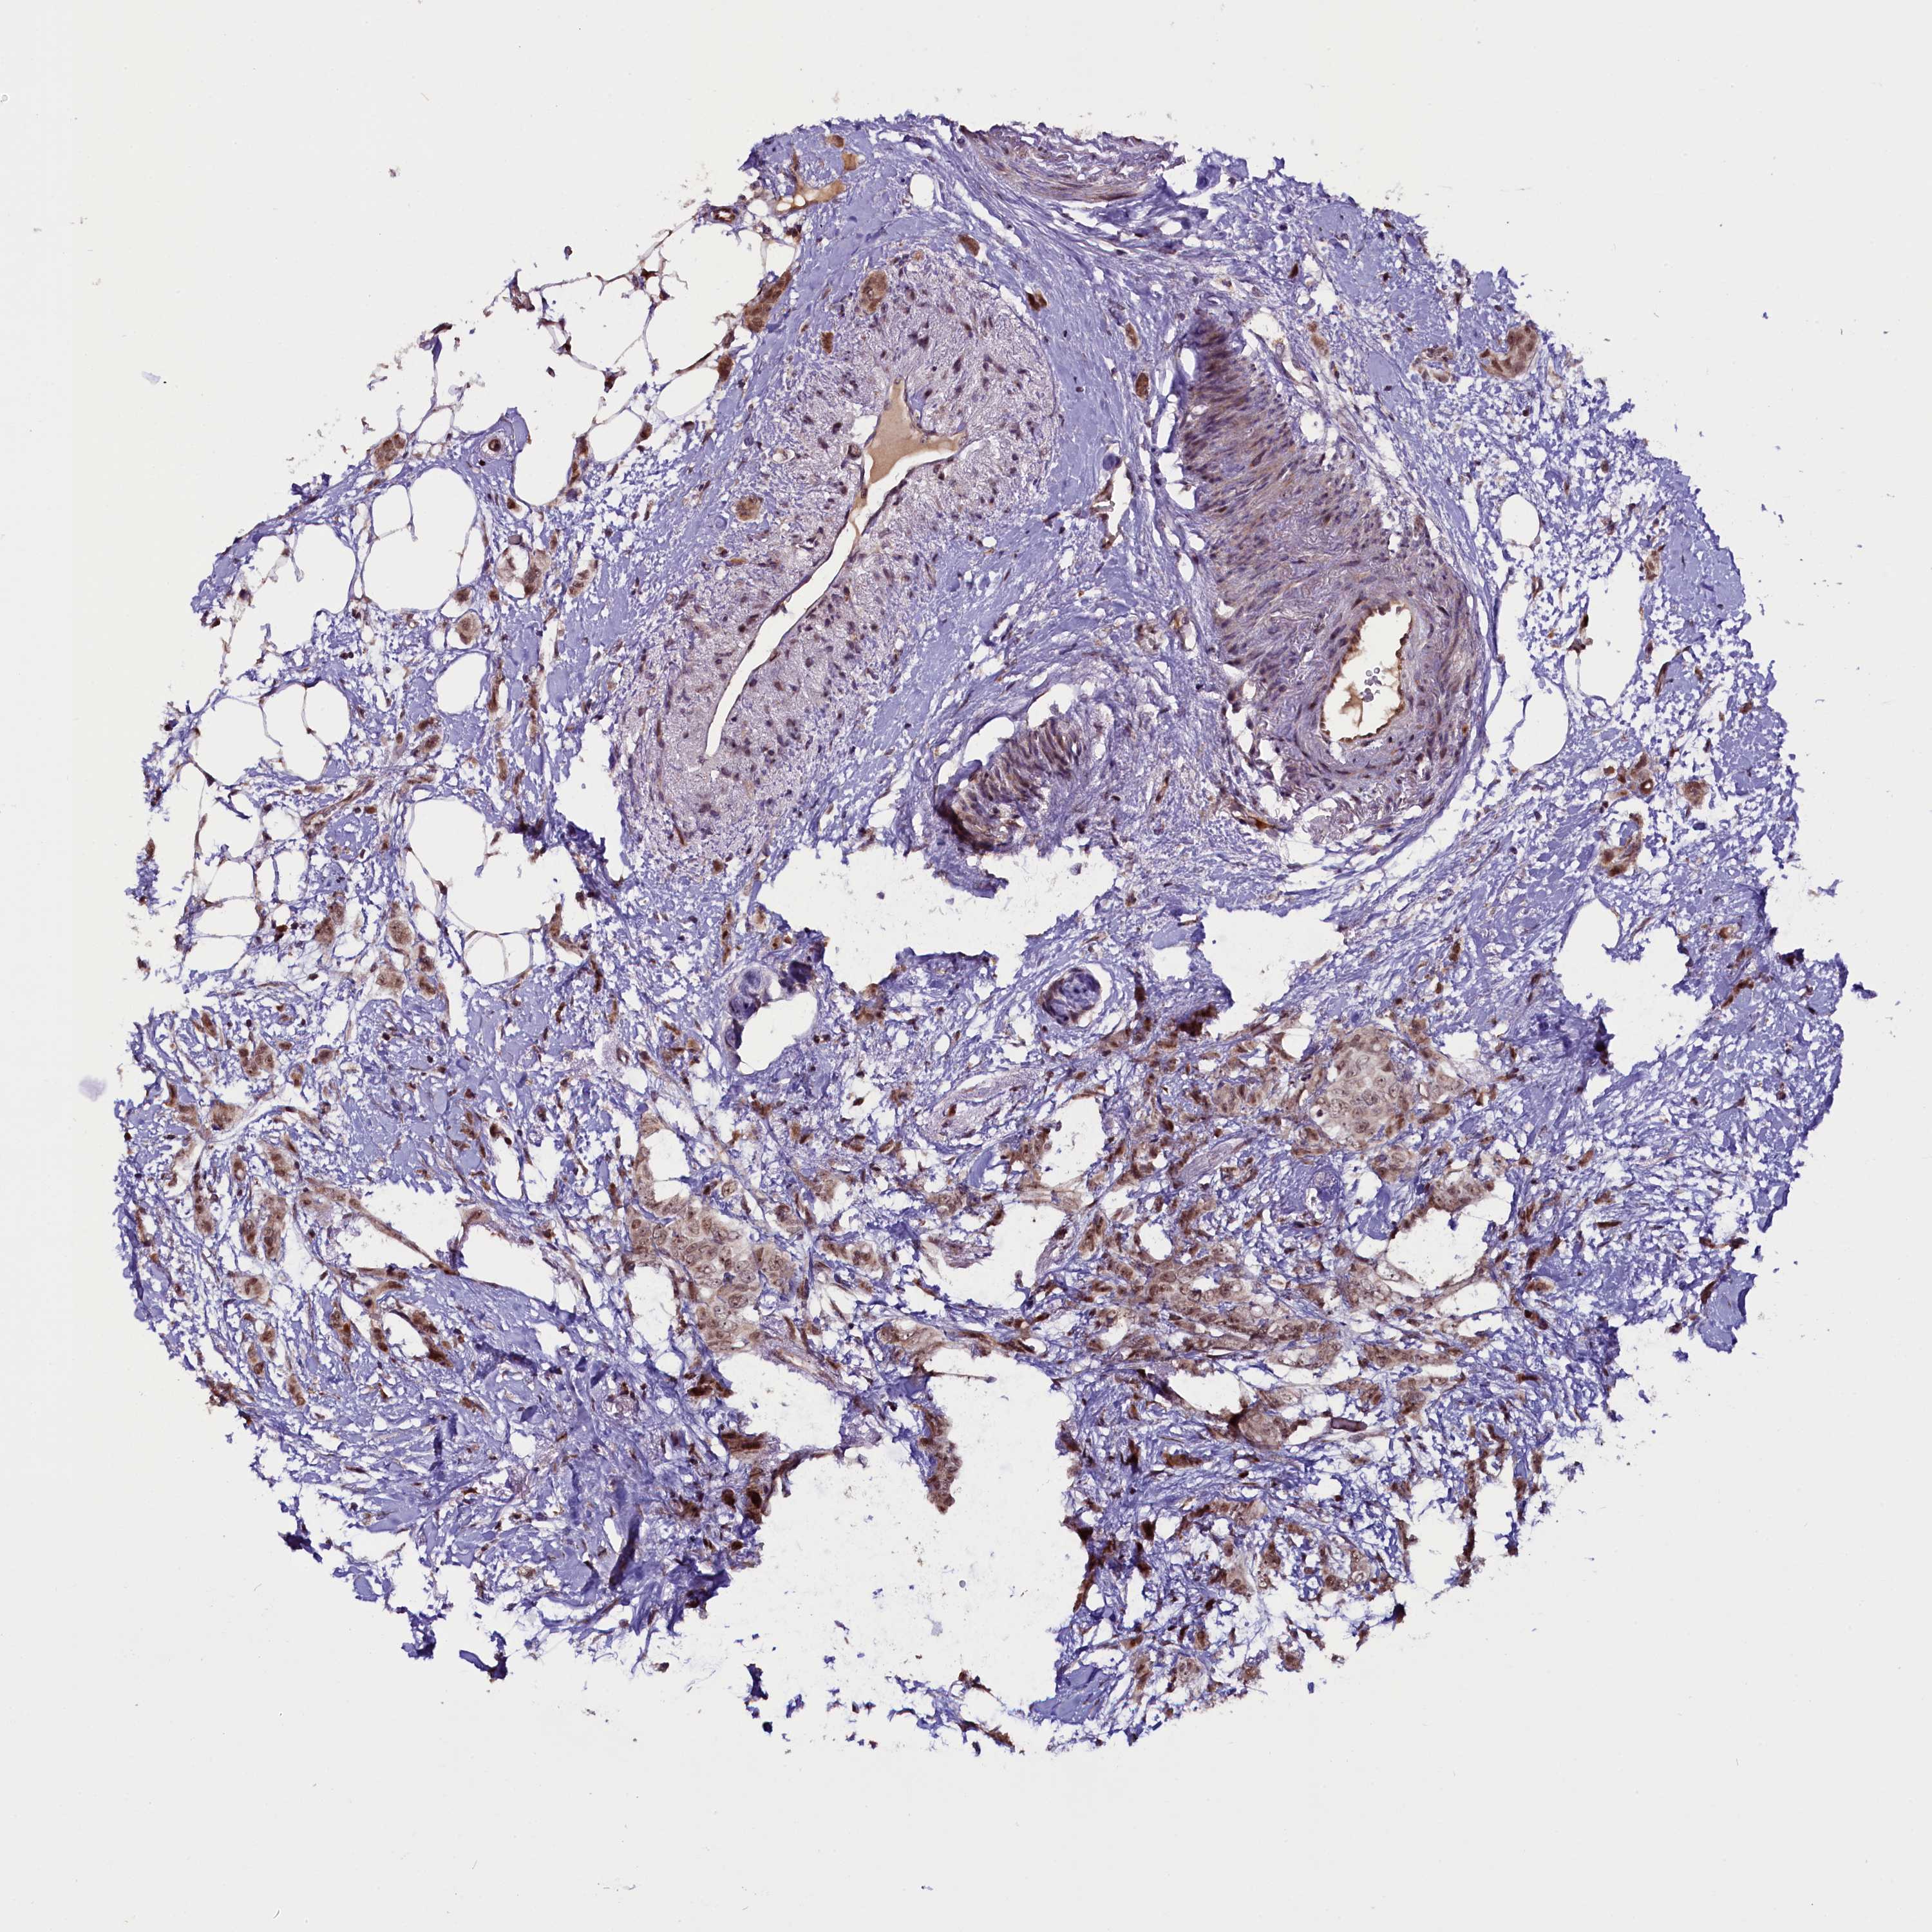

CANCER BREAST CANCER Show tissue menu

BRCA TCGA BRCA VALIDATION PROTEIN EXPRESSION

Breast cancer

Human cancer